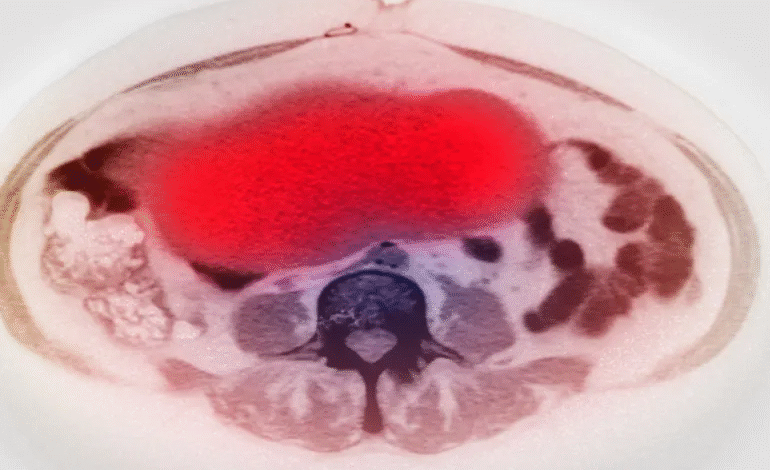

أكمل القراءة »ذكر موقع “أبونيت دي” (Abonne Santé) أن سرطان المبيض يُعد من أكثر أنواع السرطان شيوعًا بين النساء، مشيرًا إلى أن…